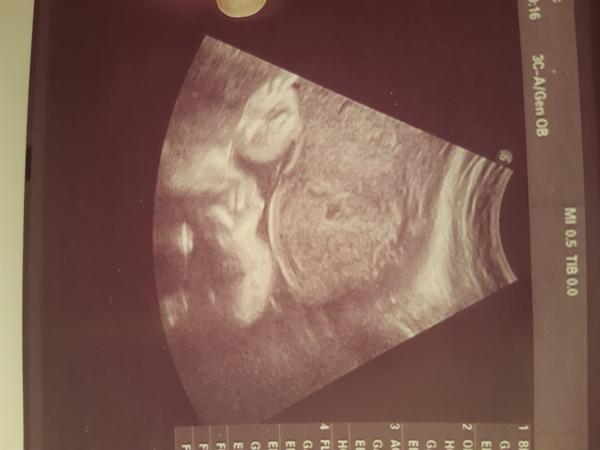

Chytřejší než doktor. Vidíte taky kluka, nebo čekat překvápko?

jsem ve 31.tt a dneska jsem zažila fakt šok. Od nějakého 18.tt žijeme s tím že naše první miminko bude moje vysnena holčička, která samozřejmě téměř hned po potvrzení doktora dostala jméno. Takže na ni celé ty dlouhé měsíce mluvím a povídám si s ní jako s holčičkou. A dnes mi doktor řekl že je to kluk, naštěstí zdravý a vše v pořádku, takže se nic neděje. Jen tu výbavu kdybych neměla komplet v ruzove😆Tak se chci zeptat jestli tam toho kluka vidíte taky, nebo mám v porodnici čekat prekvapko😆Doktora mám uzasneho ale nějak už mu v tomhle stopro neverim

Ta na obrázku je zachycena podle mě ruka ✋ 😉 Ale těžko hodnotit, když člověk nevidí další souvislosti. UZ obraz je 2D obraz v čase, takže se z jedno obrázku nedá absolutně soudit. Jinak důvěru v doktora ztrácet nemusíš. Prostě na UZ nejsou některé věci jiste. Vim to z praxe, UZ mě živí 😉

Jsem jenom laik, ale jestli má být na fotce pohlaví, tak uprostřed jde krásně vidět kávové zrnko = holka.

Doufám, že nebudím plané naděje, ale jestli to má být foto pohlaví, tak za mě holka.

@lenapol me tonprijde jako dost nešikovně fotka na pohlaví ale vidím.spis zrno. Ale takhle ke koncin jsou ty ultrazvuku těžký jak tam ma mimco čím dál min místa. Ja mam doma syna, který se ne a ne ukázat az někdy ve 28tt najednou na nas vykoukl pinda pres celou obrazovku a to bylo z boku pak zajel mezi nožky a potvrdil to. Ted cekam holcicku ( mimochodem na kazde kontrole se ptám zda to je stále holka mam sice neutrální obleceni po synovi ale taky uz mam mraky ciste holciciho a co hlavne dětský pokoj zařízený s holcicima doplnkama 🤣) ale proste furt 100% je az porod ultrazvuk je stále. Ale teda po přečtení zkusenosti mam uplne hrůzu co ze me do toho měsíce vyleze 🤣🤣🤣🤣

@rebe já si taky říkám, že se tady dá vložit klidně i fotka placenty a zeptat se, vidíte holku nebo kluka a dočkám se i odpovědí... Lidi neblázněte, pohlaví nelze určit ultrazvukem vždy na 100%, je to hodně limitováno polohou dítěte, akustickými podmínkami atd. Je třeba s tím počítat.